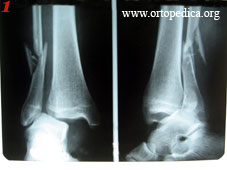

Пример №10 МОС лодыжек